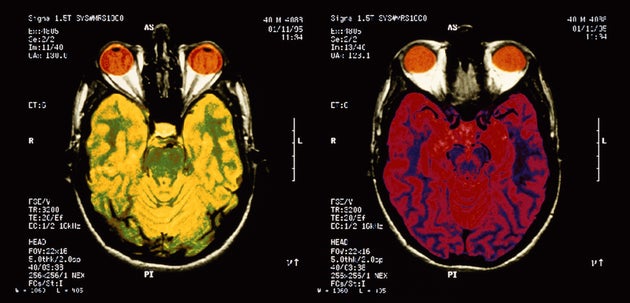

4. El cerebro y el sistema inmunológico en realidad están vinculados.

Este año, neurocientíficos de la Universidad de Virginia descubrieron una conexión directa hasta ahora desconocida entre el cerebro y el sistema inmune -

una red de vasos linfáticos que anteriormente sólo se habían encontrado que

existieran por debajo de la base del cráneo, pero que se observaron por primera

vez en el cerebro.